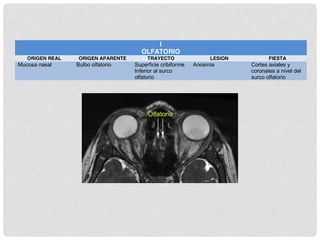

I OLFATORIO

• Forma un tracto y no un

nervio.

• Por tradición el bulbo y el

tracto olfatorio se conocen

como “nervio olfatorio”

MOLÉCULAS

AROMÁTICAS SE

DISUELVEN

RECEPTORES

SENSITIVOS DEL

EPITELIO OLFATORIO

TRASMITEN A

PROCÉSOS

CENTRALES QUE

ATRVIESAN EL

PLATILLO CRIBIFORME

DEL ETMOIDES

SINAPSIS EN

NEURONAS

SECUNDARIAS DEL

BULBO OLFATORIO

Tracto olfatorio

Estría lateral

Área olfatoria lateral

(uncus, área entorrinal

y lumen insulae = área

piriforme)

Estría intermedia

Área olfatoria

intermedia

Sustancia perforada

anterior

Estría medial

Área olfatoria medial

(septal) región

subcallosa de la

superficie medial del

lóbulo frontal.

HIPOTÁLAMO TÁLAMO

NÚCLEO

HABENULAR

PROYECCIONES: